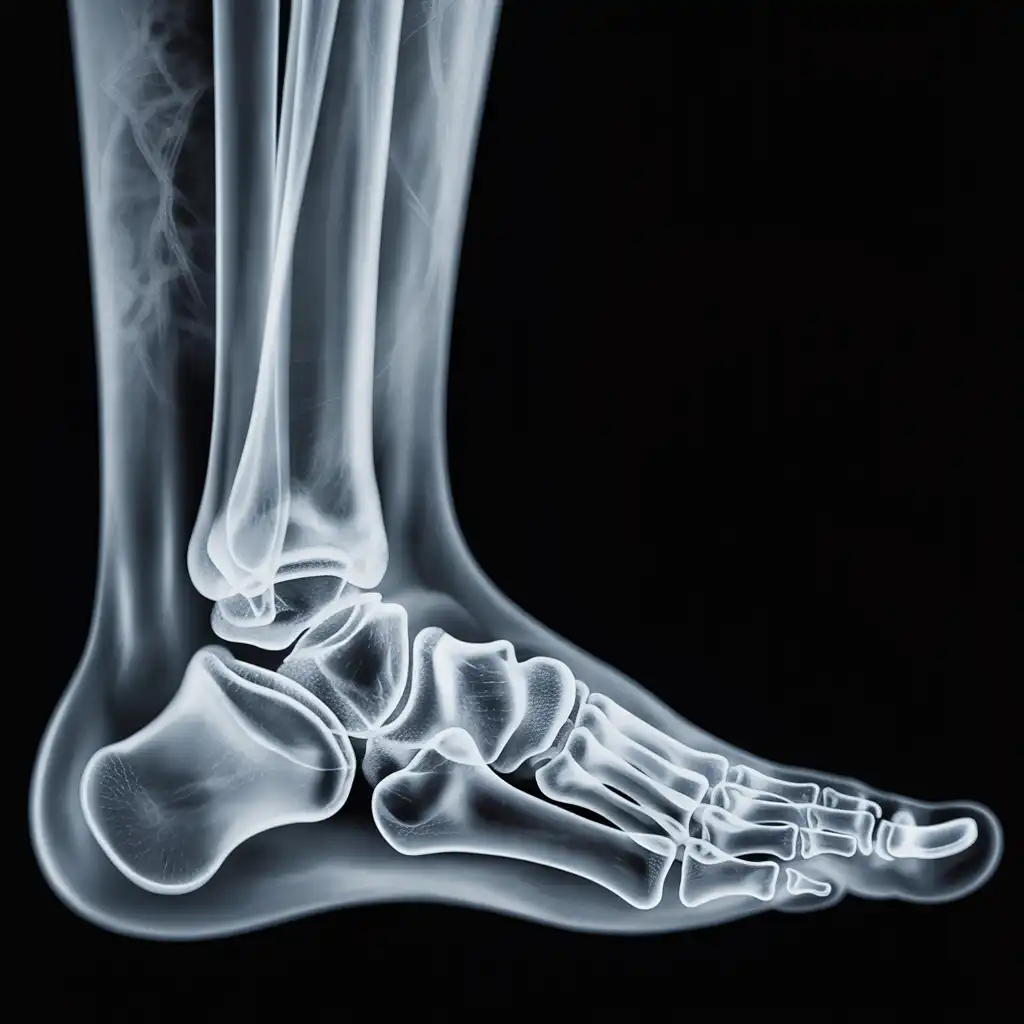

Una lastra a domicilio è una radiografia eseguita direttamente a casa del paziente, grazie all’intervento di un tecnico sanitario qualificato dotato di apparecchiatura digitale portatile.

L’esame viene effettuato sul posto, senza necessità di spostare la persona dal letto o dalla poltrona, e garantisce una qualità diagnostica paragonabile a quella di un reparto ospedaliero.

Una volta acquisite, le immagini vengono trasmesse al medico radiologo, che le analizza e redige il referto in tempi brevi.